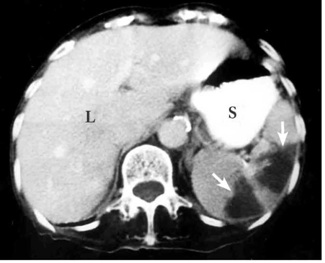

גרורות בטחול מופיעות בדרך כלל כנגעים רבים, ובדרך כלל קיימים במקרים אלו נגעים גם בכבד. ב- 20% ממקרי הגרורות בטחול הופיע הנגע בצורת כיסית, אך הרוב מופיעים כאזורים מוגדרים, בעלי קליטה פחותה בטומוגרפיה הממוחשבת. באוטם הטחול ניתן לראות פגמים בצורת משולש בטחול (תצלום 4.11).